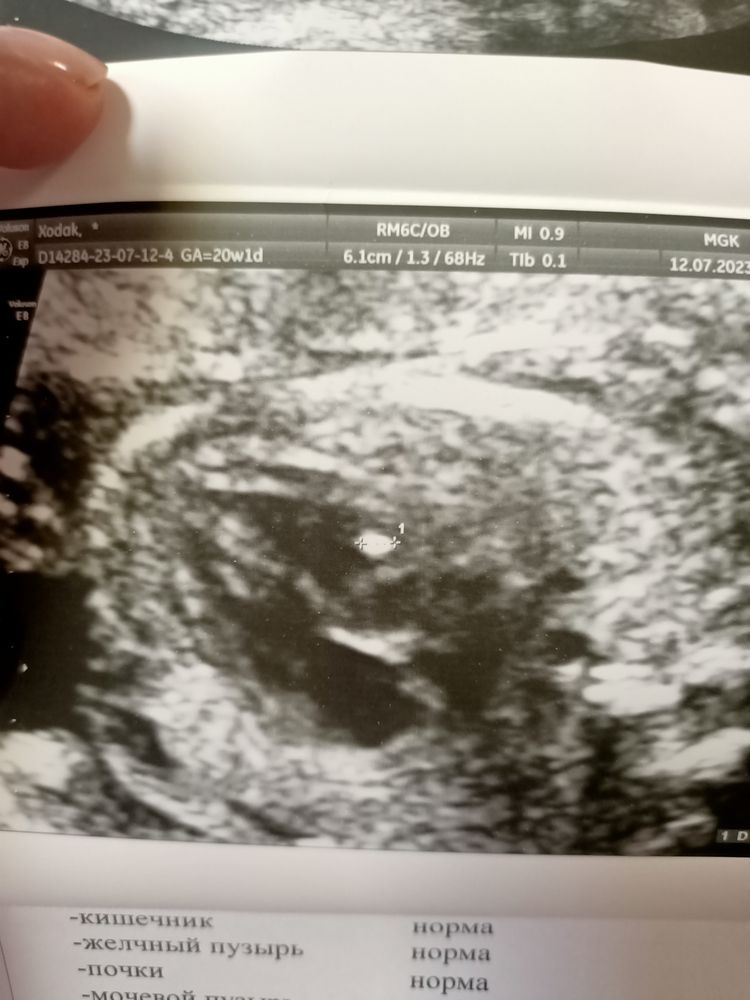

Полина Викторовна , на фото белое пятнышко. Мощный аппарат, поэтому на нем все видно.. Изображение

Ивс, анэхогенное включение должно быть черного цвета. Белого цвета - это какая-то ткань

Полина Викторовна , Гиперэхогенный фокус в желудочке сердца, так написано в заключении